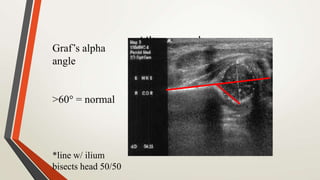

UltrasoundGraf’s alpha

angle

>60 = normal

*line w/ ilium

bisects head 50/50

UltrasoundGraf’s alpha angle >60 =normal *line w/ ilium bisects head 50/50